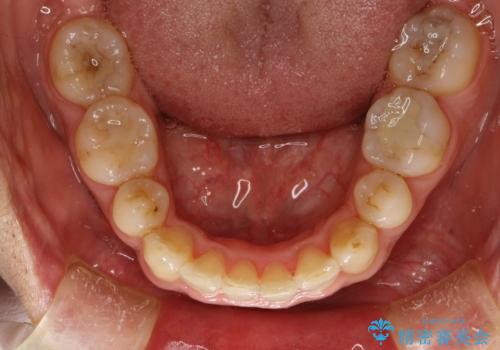

- 以前、上下左右4本抜いてワイヤー矯正をしていた方で、後戻りで下の前歯のガタガタを気にして来院されました。

マウスピース矯正にて、下の歯はIPR(歯と歯の間を削る)を入れることでガタガタの改善、咬み合わせの深さも改善をはかる治療計画をたてました。

歯と歯の間を削って隙間を作って矯正をしています。